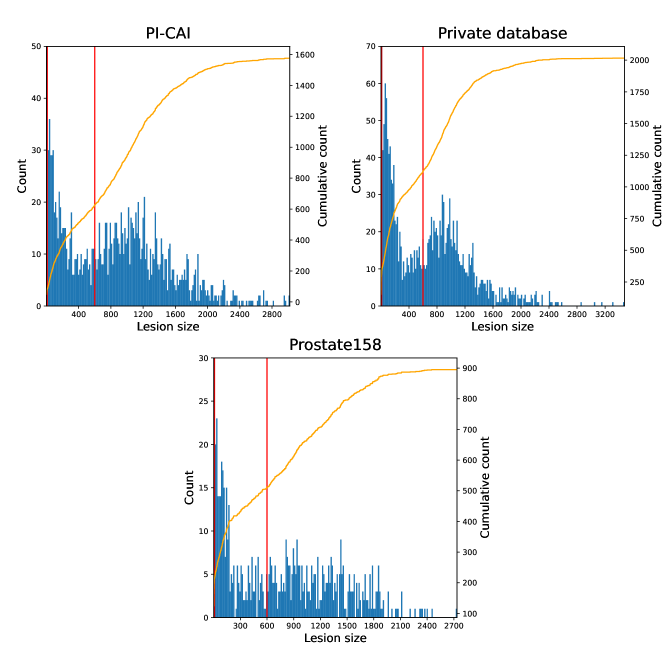

Both T2-weigthed (T2w) and apparent diffusion coefficient (ADC) MR maps were used as input channels. The latter modality was registered to the former, all images were resampled to a mm3 pixel size and cropped to volumes. Images intensities were linearly normalized into the range [0, 1] for each patient and each modality. More details about these datasets can be found on Appendices A and B, including lesion volume distributions and histograms of intensities for T2-weighted imaging and ADC maps.

Appendix A Lesion characteristics for each database

| Database | # of positive cases / total patients | # of CS lesions |

|---|---|---|

| PI-CAI | 220 / 1295 (17%) | 301 |

| Private dataset | 183 / 219 (84%) | 408 |

| Prostate158 | 82 / 139 (59%) | 236 |

Appendix B Characteristics of MRI modalities for each database